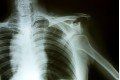

Rozpoznanie uszkodzenia stawu barkowo – obojczykowego jest możliwe na podstawie dokładnego wywiadu, badania klinicznego oraz występujących objawów. Miejscowy ból, tkliwość oraz nieznaczny obrzęk stawu mogą świadczyć o uszkodzeniu lekkim (I typu). Nasilone dolegliwości bólowe, utrzymywanie kończyny w przywiedzeniu, a przede wszystkim widoczne odstawanie dalszego końca obojczyka będą sugerować poważniejsze uszkodzenie stawu. Należy pamiętać o możliwości wystąpienia urazów współistniejących jak: złamanie obojczyka, zwichnięcie stawu mostkowo – obojczykowego czy uszkodzenie struktur naczyniowych i nerwowych. Oprócz badania klinicznego, najistotniejszym elementem oceny stopnia uszkodzenia stawu barkowo – obojczykowego jest diagnostyka radiologiczna. Zdjęcia rentgenowskie wykonuje się najczęściej w płaszczyznach: przednio – tylnej (A-P) oraz bocznej. W razie wątpliwości pomocne okazuje się badanie ultrasonograficzne, dzięki któremu możliwa będzie ocena niestabilność dalszego końca obojczyka oraz uszkodzenia więzadeł. Do dyspozycji są również zaawansowane metody diagnostyki obrazowej jak: rezonans magnetyczny i tomografia komputerowa, które w sposób kompleksowy powinny określić rozległość urazu. Ich minusem jest mała dostępność i wysoka cena, co wpływa na ich rzadkie wykorzystywanie przez lekarzy.